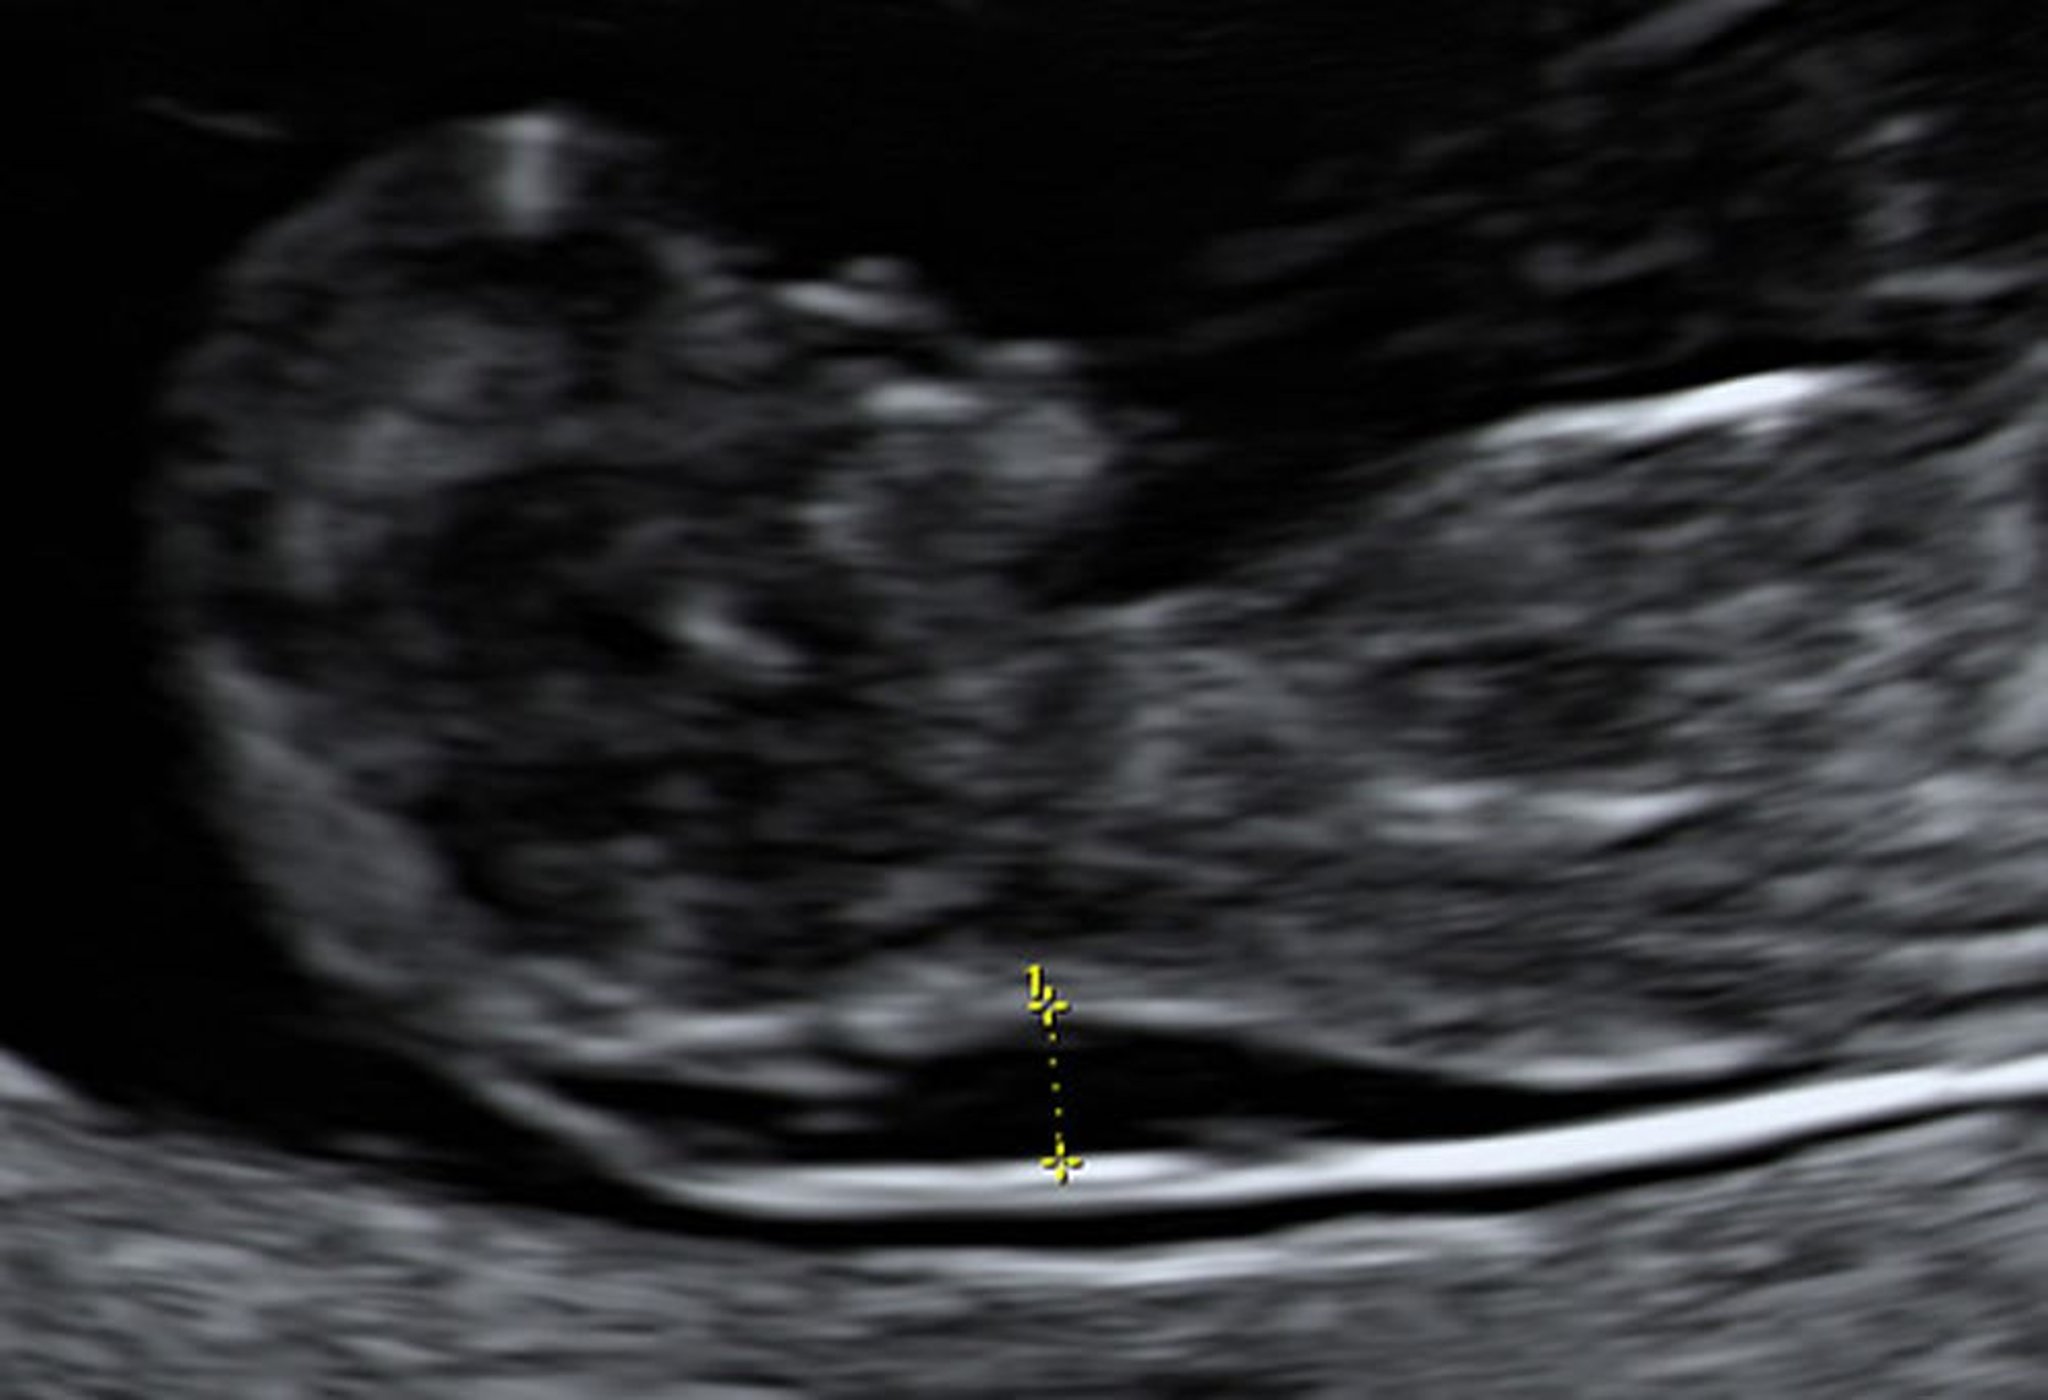

Échographie montrant une clarté nucale augmentée chez un fœtus à 10 semaines

Un prélèvement de villosités choriales a montré que ce fœtus avait un syndrome de Down.

Photo d'après Jeffrey S. Dungan, MD.